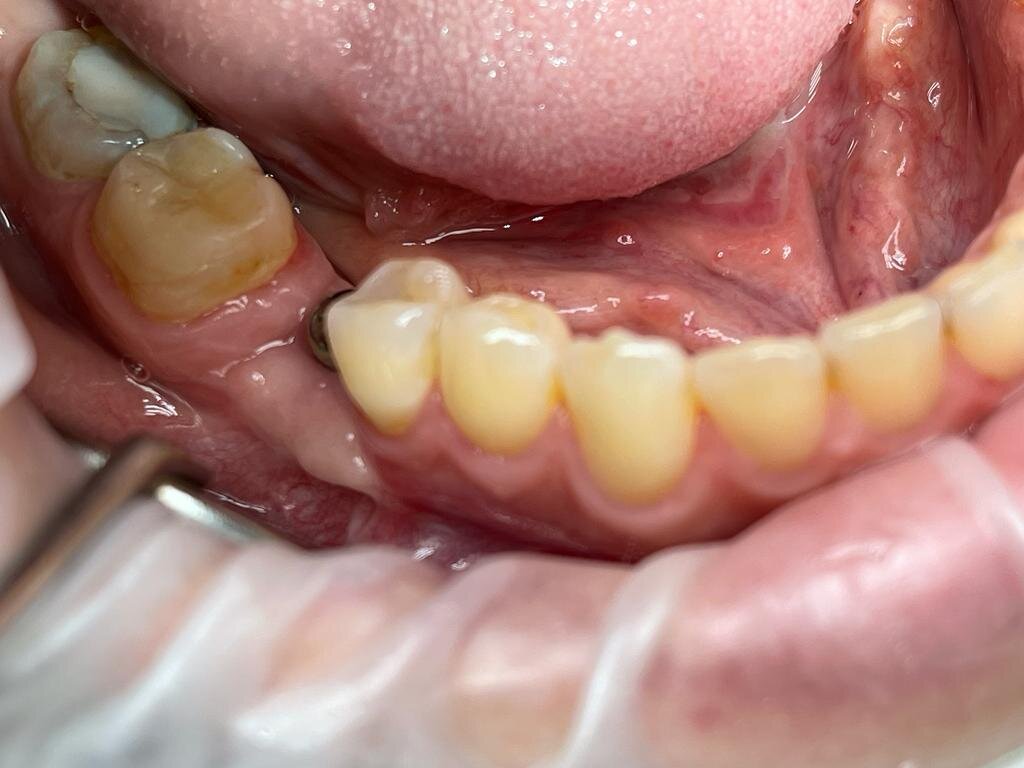

Задача хирурга удалить ненужную слизистую на проблемном участке, вырезать кусочек десны (обычно 5*10мм) с нёба либо бугра верхней челюсти и пришить в место где была слизистая. Через 2 недели швы снимаются и имплант протезируется либо коронка ставится повторно (если коронка стояла до операции, то она снимается и ставится формирователь десны). Донорский участок на нёбе или бугре заживает также через 2 недели, а еще через 2 в этой области можно брать трансплантат еще раз.

Фото можно листать пальцем либо мышкой!

Таким образом я добился прикрепленной кератинизированной десны. Импланту на данный момент уже 5 лет и ни один виток импланта не оголился.